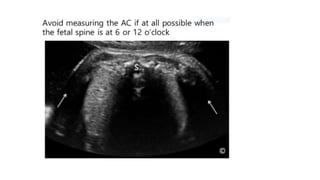

Abdominal Circumference

• The single most important measurement to make in late pregnancy. It reflects more of fetal size and weight

Abdominal Circumference • Thesingle most important measurement to make in late pregnancy. It reflects more of fetal size and weight rather than age. Serial measurements are useful in monitoring growth of the fetus.